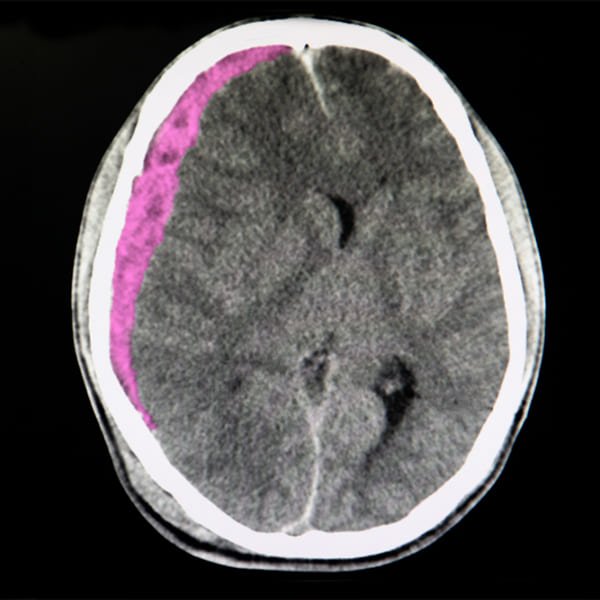

Hematomas subdural y epidural

Un hematoma subdural o epidural espinal es una acumulación de sangre en el espacio subdural o epidural que puede comprimir mecánicamente la médula espinal.

El diagnóstico se realiza con una RM o, cuando no se encuentra fácilmente disponible, con una mielografía por TC. El tratamiento se efectúa con drenaje quirúrgico inmediato.